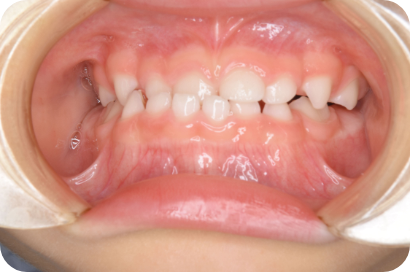

Nさん

Before

After

- 形態:咬合改善

- 機能:習癖の改善、咀嚼トレーニング、口腔周囲筋エクササイズ

- メリット:顎の正常な成長を促し、将来の抜歯や本格矯正のリスクを軽減します。正しい噛み合わせは全身の健やかな発育にも繋がります。

- リスクと副作用:お口周りの筋肉痛や疲労感が一時的に出ることがあります。また、毎日のトレーニングや癖の改善をご家庭で継続する必要があり、ご家族の協力が不可欠です。